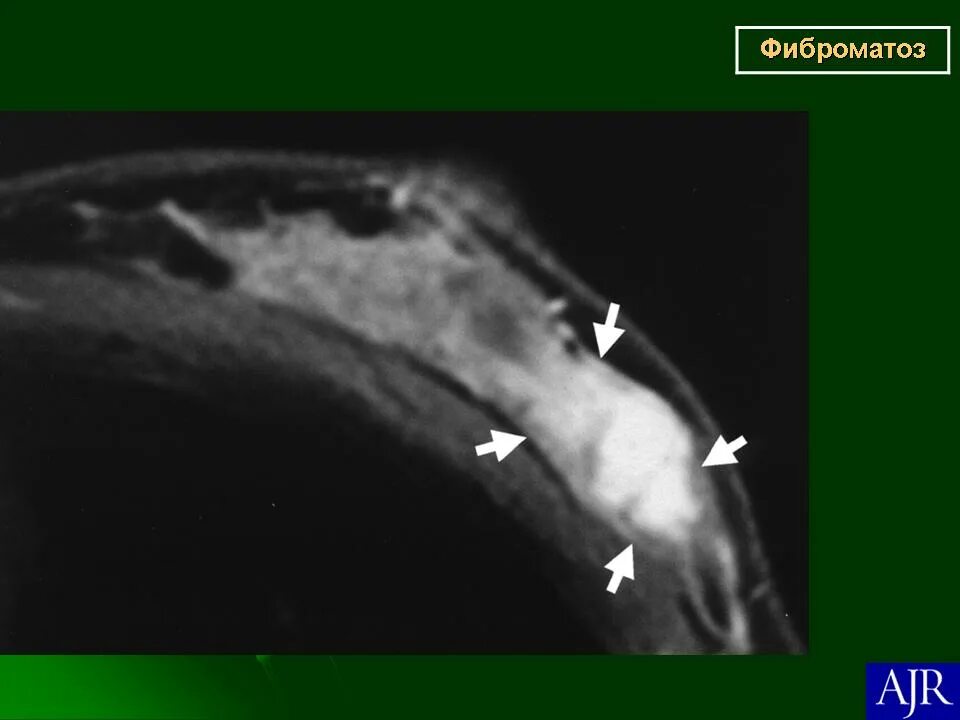

Фиброматоз мягких